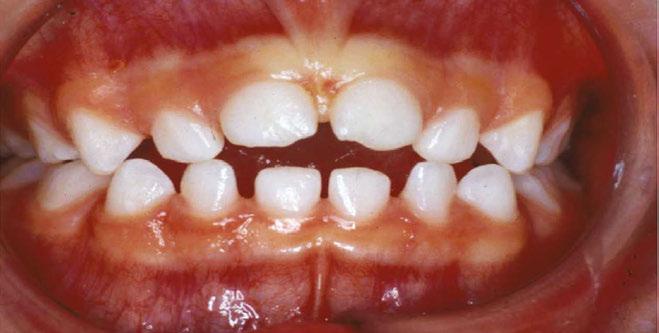

Figure 1: JA initial photos. Mixed dentition, Class I, upper spacing, lower crowding, ectopic U3s (10.7 years old)

This patient presented in mixed dentition and a Class I occlusion with mild upper spacing, lower moderate crowding, and mild deep bite. The U3s were ectopic with a palatal position and a mesial path of eruption, converging onto the U2 roots, and the patient also had a tapered upper archform, an ovoid lower

archform, and a posterior tongue tie (mid-tongue restriction). The upper midline was centered with the facial midline, but the lower midline was deviated 4 mm to the left of the upper (Figure 1).